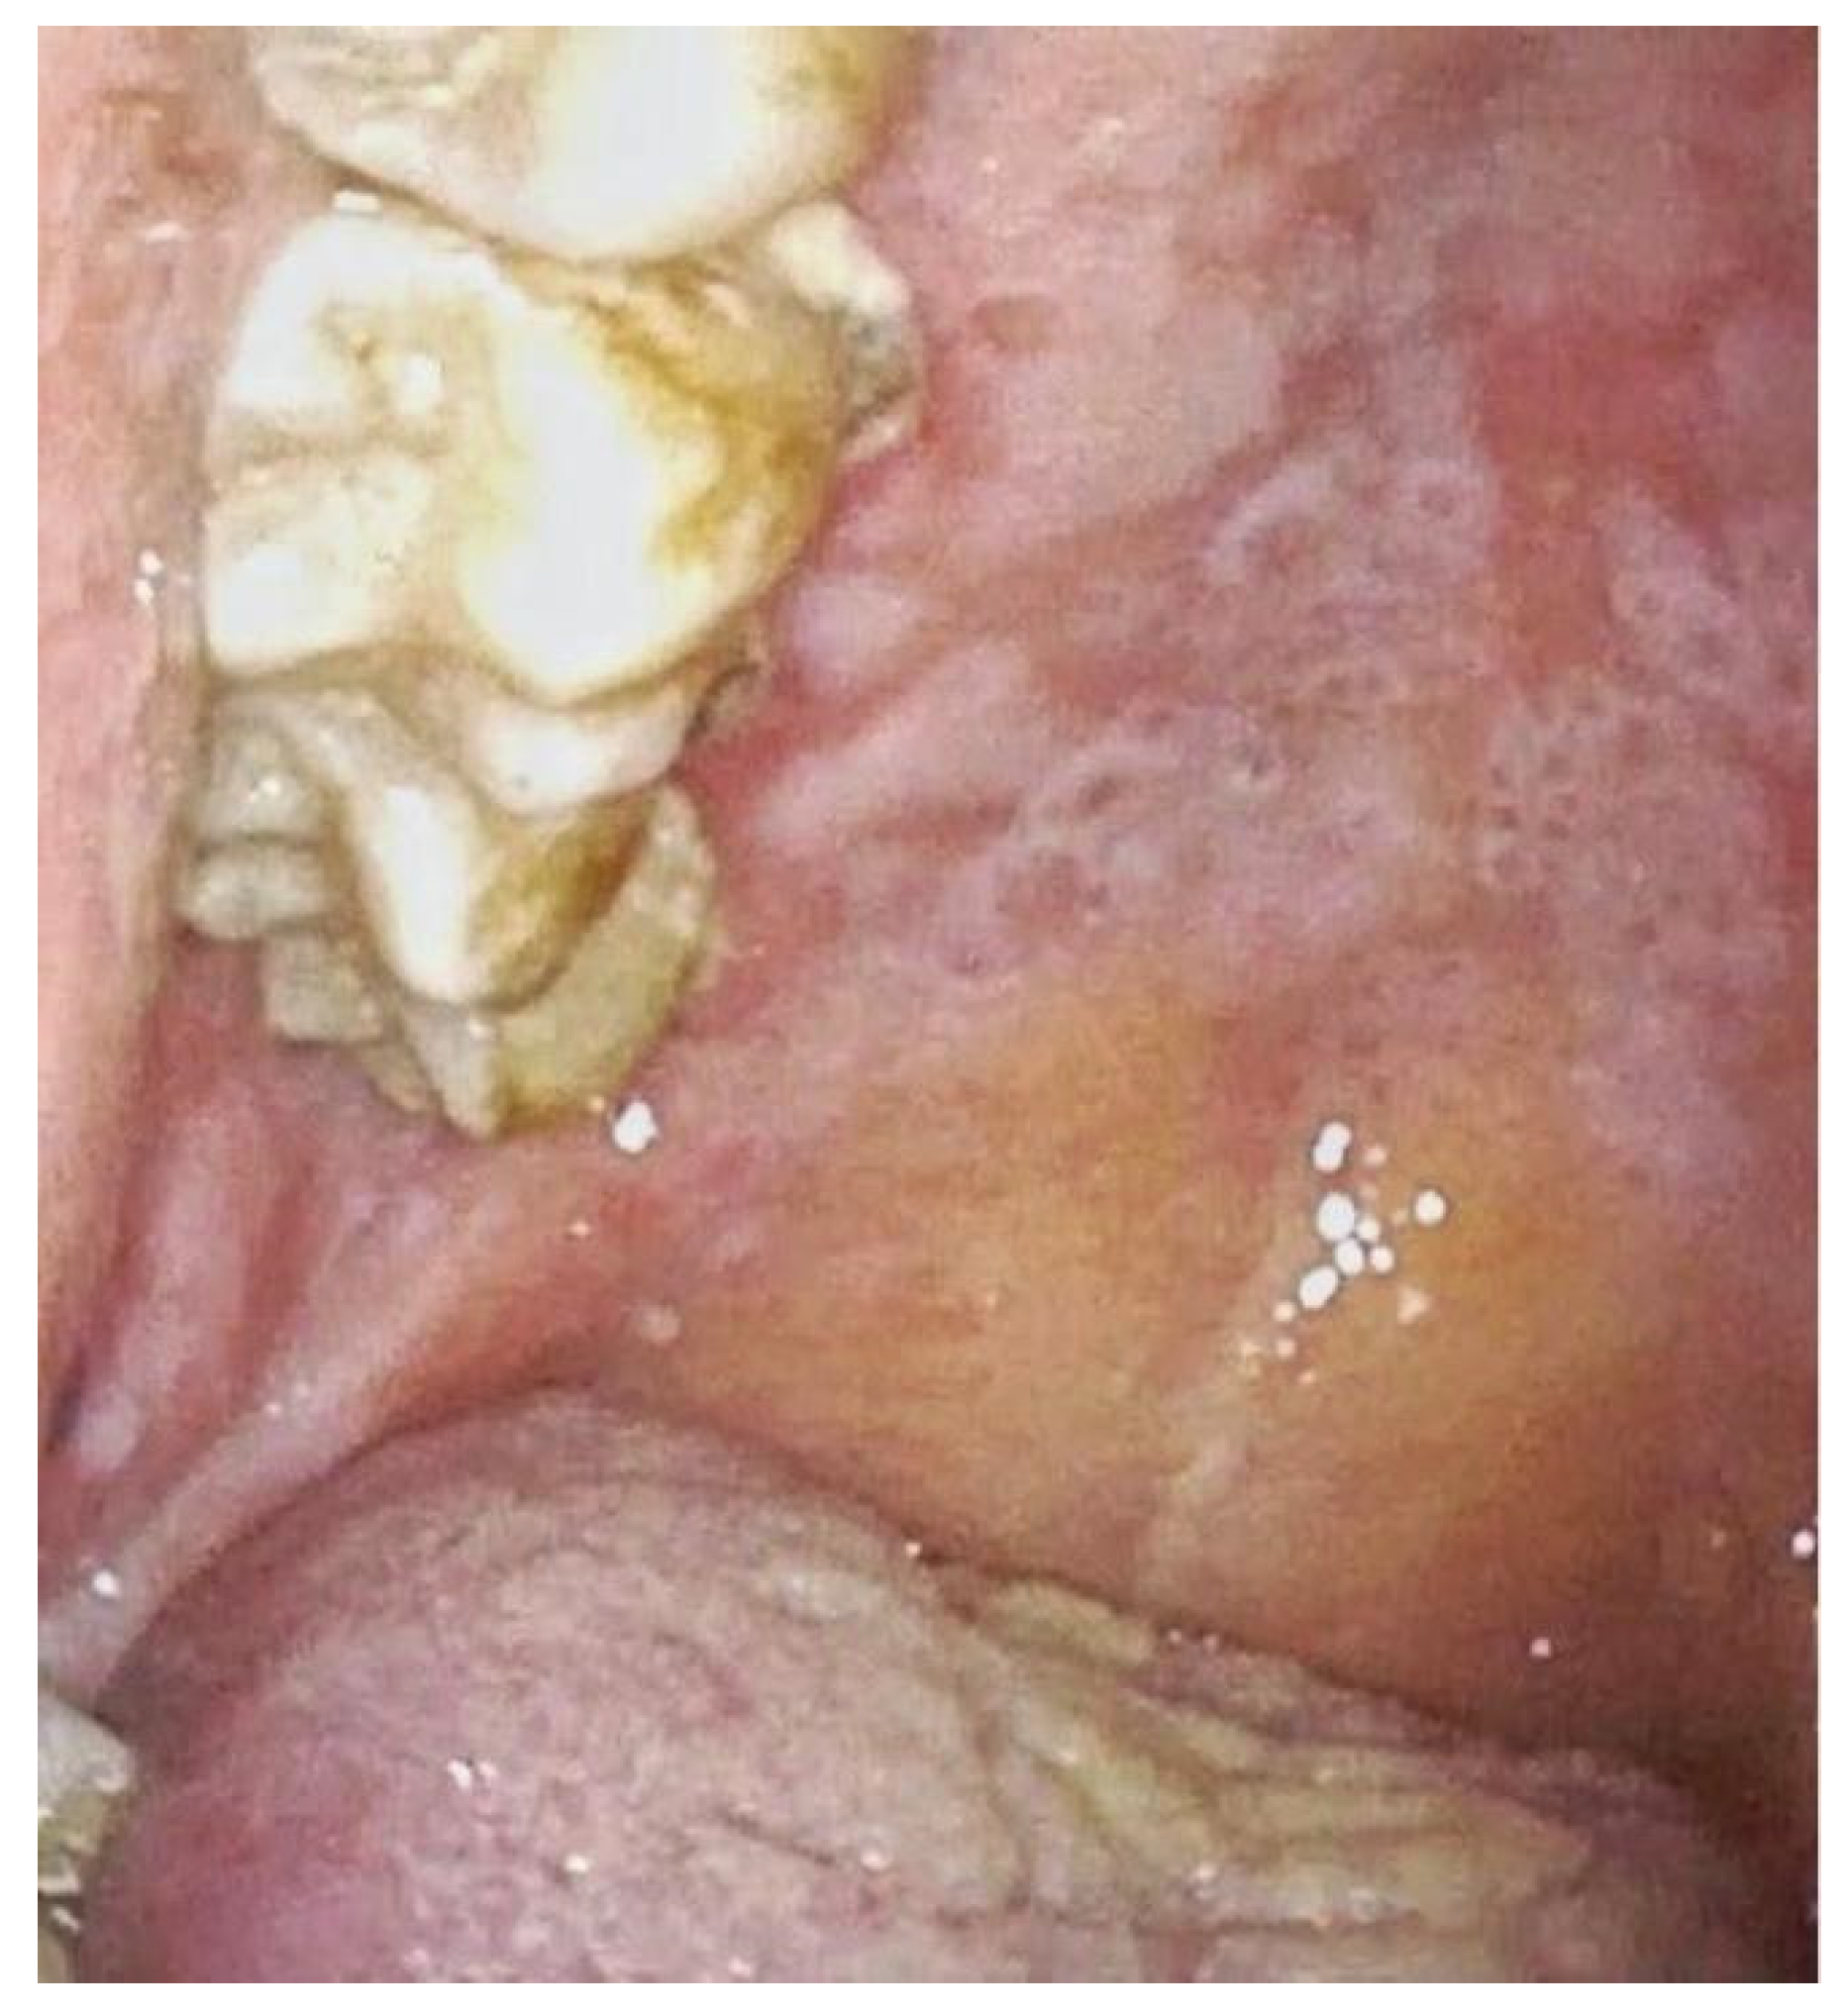

| 2 | Buccal mucosa bilaterally and left tonsillar pillar with extension at amygdalo-glossus sulcus and oropharynx | Erythroplakia paired with central erosive area | Diffuse mucositis and evidence of erythroplakia with erosive central area suspicious for malignant disease | Evidence of intrapapillary capillary loops | Squamocellular carcinoma of the oropharynx. |